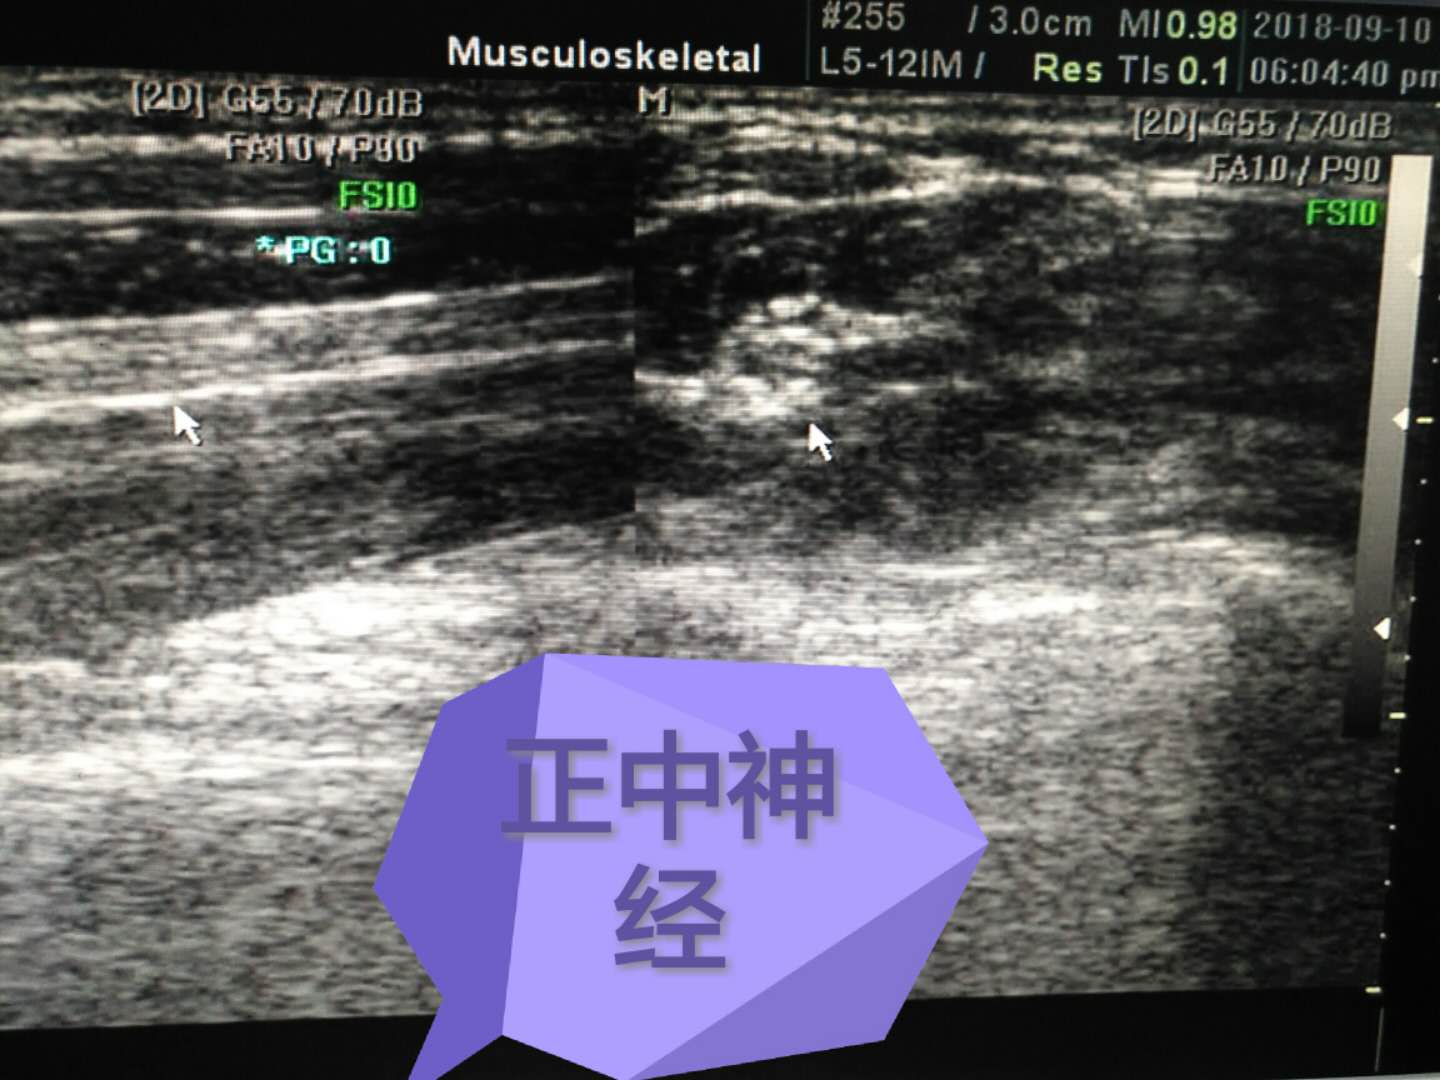

正中神經(jīng)